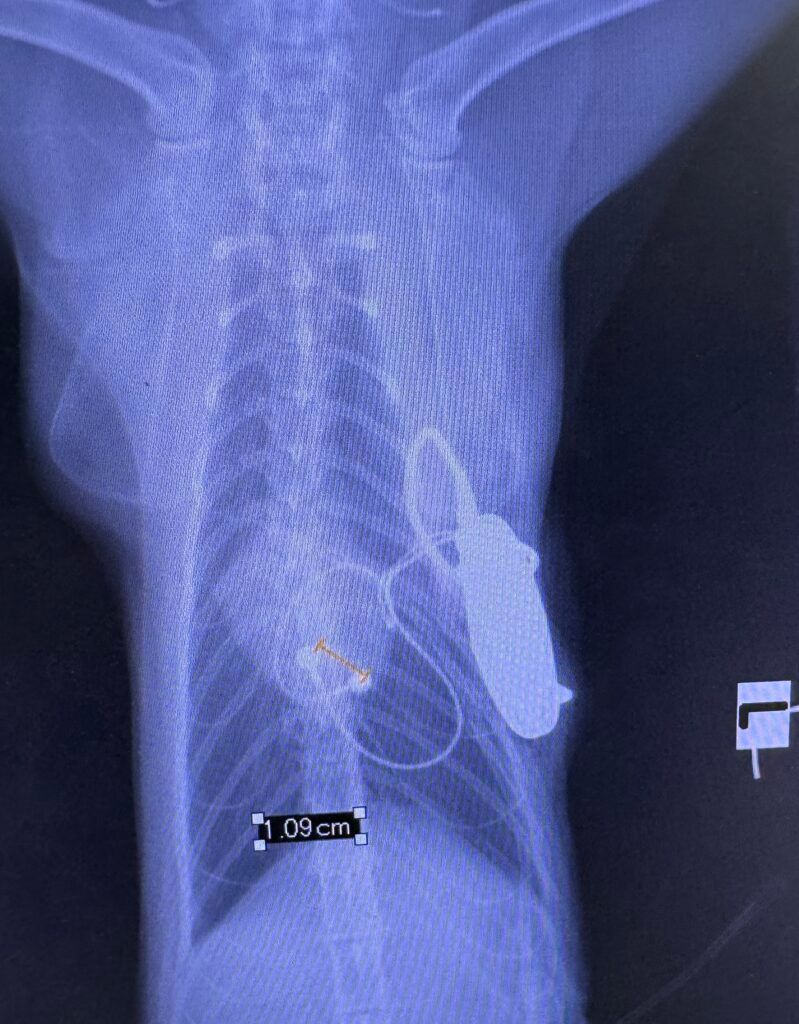

The surgical team needed to open the cat's chest cavity between the ribs to access the heart directly. Then, they attached the pacing lead to the heart’s surface and connected that to a small generator implanted under the abdominal muscles.2 The procedure in its entirety took 1 hour and involved a multidisciplinary team working in close coordination.

Pepsi’s pacemaker device is the same model that is used in humans. It was customized with appropriately sized leads, and for Pepsi, the pacemaker had been donated and sterilized for reuse. Following the procedure, Pepsi made a quick recovery. She no longer faints, interacts energetically with her owner and the other cats at the home, and eats normally. She visits the hospital every 3 months for follow-ups, but overall lives a normal life.1